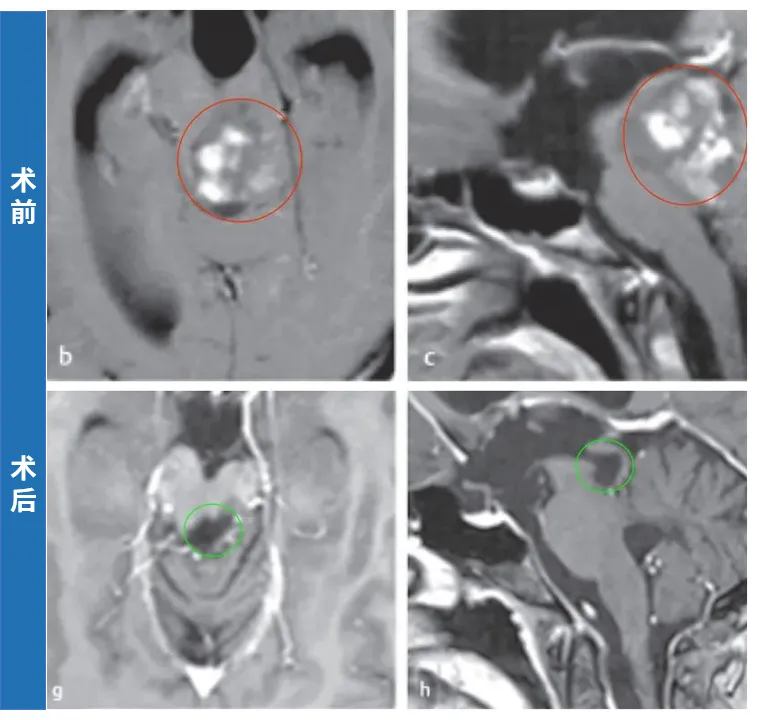

20岁的外国女孩米亚因剧烈头痛查出一个背侧外生的中脑肿瘤引起梗阻性脑积水。瘤子位置确实深,而且累及中脑和上脑桥。手术中稍不注意,或者损伤中脑患者变成植物人,损伤桥脑引起半身瘫痪,严重损伤延髓影响呼吸功能。

由于肿瘤与周围的脑干实质有很好的边界,肿瘤全切。术后11年随访时:术后MRI显示患者没有肿瘤残留或复发。点击阅读:胶质瘤19年无复发!这个女孩打破脑干“不能手术”魔咒,故事还被写入国际专著